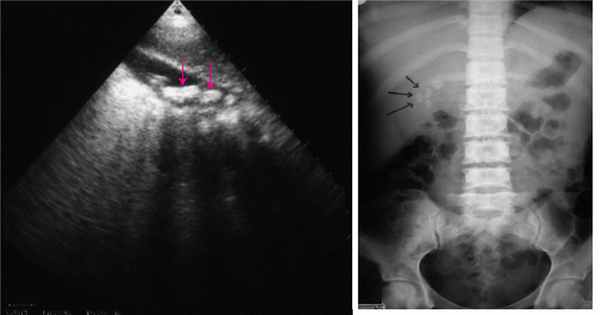

Методы визуализации (ультрасонография, КТ)

У стабильных пациентов травма печени подтверждается результатами КТ, а у пациентов с нестабильным состоянием выполняется прикроватная ультрасонография или диагностическая лапаротомия.

Диагноз выставляется на основании осмотра пациента, данных анализов крови и дополнительных исследований. Для выявления повреждения может использоваться УЗИ, компьютерная томография и ангиография. Наиболее информативным методом исследования является лапароскопия. Во время этой процедуры в брюшную полость через небольшой разрез вводится эндоскоп, через который можно непосредственно осмотреть различные органы, установить факт кровотечения и выявить его источник, а также примерно оценить объем кровопотери.